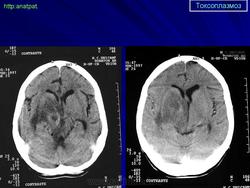

Церебральный токсоплазмоз.

Церебральный токсоплазмоз

Пато морфологи я. Патоморфологические изменения при приобретенном токсоплазмозе изучены в экспериментах на животных. Установлено, что в центральной нервной системе развиваются явления некротического перивентрикулита, мелкие очаги некроза в субкортикальном белом веществе. В сосудах головного мозга, мягкой мозговой оболочки и хориоидальных сплетениях отмечаются признаки серозно-пролиферативного воспаления. Обнаруживаются также глазные патологоанатомические изменения (типа ретинита, хориоидита, иридоциклита) и изменения во внутренних органах (сердце, легкие, печень, селезенка).

Врожденный токсоплазмоз чаще, чем приобретенный, приводит к летальному исходу. В головном мозге умерших обнаруживаются более или менее значительные очаги обызвествления, участки размягчения мозгового вещества, полости, заполненные жидкостью. Как правило, отмечается гидроцефалия, обусловленная воспалительной и рубцовой облитерацией водопровода среднего мозга, отверстий Люшка или других участков ликворных путей. Истон-чение вещества полушарий мозга может достигать степени их полного исчезновения.

Особенно характерна триада симптомов: хореоретинит, гидроцефалия, очаги обызвествления в головном мозге. Кроме того, отмечаются менингеальные знаки, тонические и клонические судороги, парезы, параличи, олигофрения.